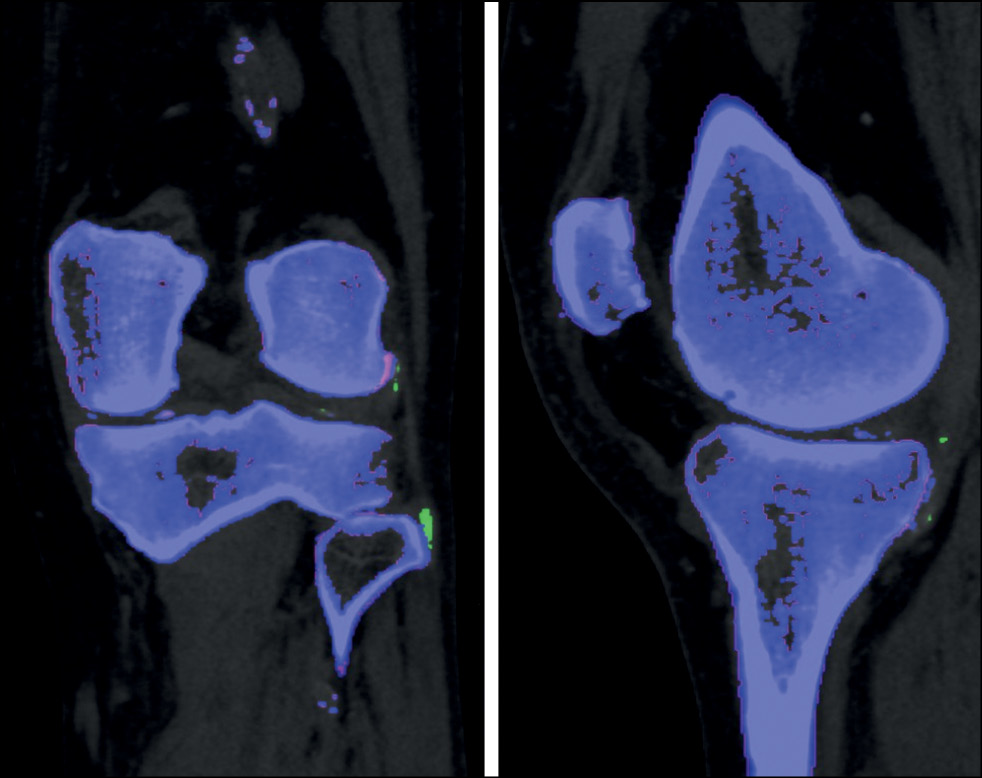

The role of DECT in the diagnosis of calcium pyrophosphate crystal deposition disease is unclear. Calcium-containing deposits will be colored blue on color-coded images obtained with DECT in the dual-energy gout class, allowing them to be distinguished from monosodium urate-containing deposits. The cortical bone is color-coded similarly to calcium pyrophosphate and hydroxyapatite deposits because of its high calcium concentration (Fig. 4).

Fig. 4. Color-coded dual-energy coronal and sagittal images (left knee joint). Calcification of the medial meniscus (dual-energy computed tomography findings of the Medical Research and Education Center of the Lomonosov Moscow State University).